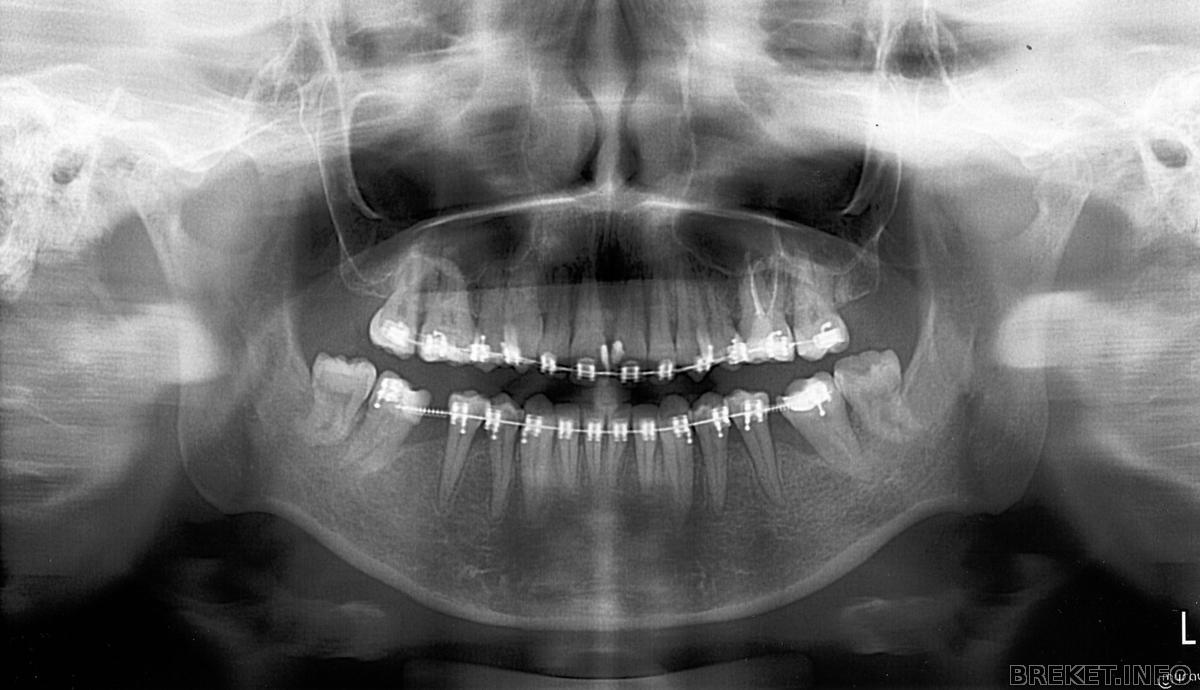

img438.jpg

врач долго и упорно смотрел на промежутки между пятерками и семерками, и пришел к выводу, что и импланты рисковано ставить, и тянуть рисковано, костной ткани не густо, сообща решили тянуть.

а в целом я снимком разочарована, ожидала чего-то более впечатляющего!

самое противное, что из-за качества не удается рассмотреть толком корни зубов, не рассосались ли они у меня,я так и не поняла.